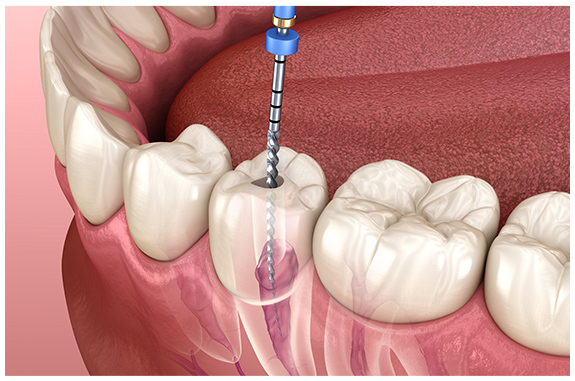

重度のむし歯に対応する根管治療

重度のむし歯に対して行う

根管の治療です

むし歯は進行すると根管まで達し、痛みがでます。その状態まで進行すると抜歯を勧められることも多いのですが、根管の状態をしっかり確認して治療していくことで歯を保存できる可能性があります。

なんとか自分の歯を残したい、残せる方法を探りたいという場合には根管治療が最後の砦となるのです。

精密な根管治療のための

機器・器具